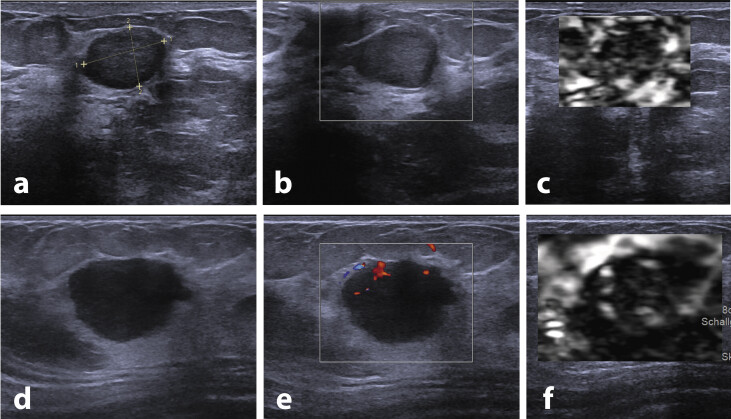

Ultrasound is a highly effective imaging tool for assessing abnormalities within the breast. However, especially the identification of malignant tumors of the breast mimicking fibroadenomas (MTMF) by means of breast ultrasound can be challenging. This study aimed to identify reliable imaging characteristics of MTMF.This retrospective study was approved by the local ethics review board. After screening 623 patients, 421 cases with histologically verified fibroadenomas and MTMF between 2011 and 2021 were included. Sonographic features were compared to histopathological results and an algorithm-based quantitative ranking of predictors contributing most to the correct classification of malignant tumors was conducted.A total of 363 benign, 18 intermediate, and 40 malignant lesions were analyzed. Algorithm-based quantitative ranking showed that the most predictive features indicating malignancy were a hyperechoic rim (gain ratio merit 0.135 ± 0.004), an irregular border (0.057 ± 0.002), perilesional stiffening (0.054 ± 0.002), pectoral contact (0.051 ± 0.003), an irregular shape (0.029 ± 0.001), and irregular vasculature (0.027 ± 0.002).Ultrasound findings for fibroadenomas vary, making identification of MTMF challenging. Features such as indistinct margins and increased perilesional echogenicity are predictors for malignancy and should be considered during sonographic evaluation of fibroadenomas and MTMF.